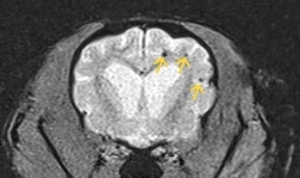

✎ 圖四及圖五腦部微出血在MRI特殊序列下無所遁形!

- MRI 是診斷黃金工具:能清楚觀察缺血/出血位置與範圍,一些特殊序列如加權梯度回波序列(T2*W、GRE)、擴散加權成像(DWI)等對出血及缺血性病灶極具診斷力